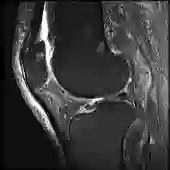

Current methods for multimodal medical imaging based disease recognition face two major challenges. First, the prevailing "fusion after unimodal image embedding" paradigm cannot fully leverage the complementary and correlated information in the multimodal data. Second, the scarcity of labeled multimodal medical images, coupled with their significant domain shift from natural images, hinders the use of cutting-edge Vision Foundation Models (VFMs) for medical image embedding. To jointly address the challenges, we propose a novel Early Intervention (EI) framework. Treating one modality as target and the rest as reference, EI harnesses high-level semantic tokens from the reference as intervention tokens to steer the target modality's embedding process at an early stage. Furthermore, we introduce Mixture of Low-varied-Ranks Adaptation (MoR), a parameter-efficient fine-tuning method that employs a set of low-rank adapters with varied ranks and a weight-relaxed router for VFM adaptation. Extensive experiments on three public datasets for retinal disease, skin lesion, and keen anomaly classification verify the effectiveness of the proposed method against a number of competitive baselines.

翻译:当前基于多模态医学成像的疾病识别方法面临两大挑战。首先,主流的“单模态图像嵌入后融合”范式无法充分利用多模态数据中的互补与关联信息。其次,标注多模态医学图像的稀缺性,加之其与自然图像存在显著的领域偏移,阻碍了前沿视觉基础模型(VFMs)在医学图像嵌入中的应用。为协同应对这些挑战,我们提出了一种新颖的早期干预(EI)框架。该框架将一种模态视作目标模态,其余作为参考模态,利用参考模态的高层语义标记作为干预标记,在早期阶段引导目标模态的嵌入过程。此外,我们引入了混合低变秩自适应(MoR),这是一种参数高效的微调方法,它采用一组具有不同秩的低秩适配器和一个权重松弛路由器来实现对VFM的自适应。在视网膜疾病、皮肤病变及膝关节异常分类三个公开数据集上进行的大量实验验证了所提方法相对于多个竞争基线的有效性。